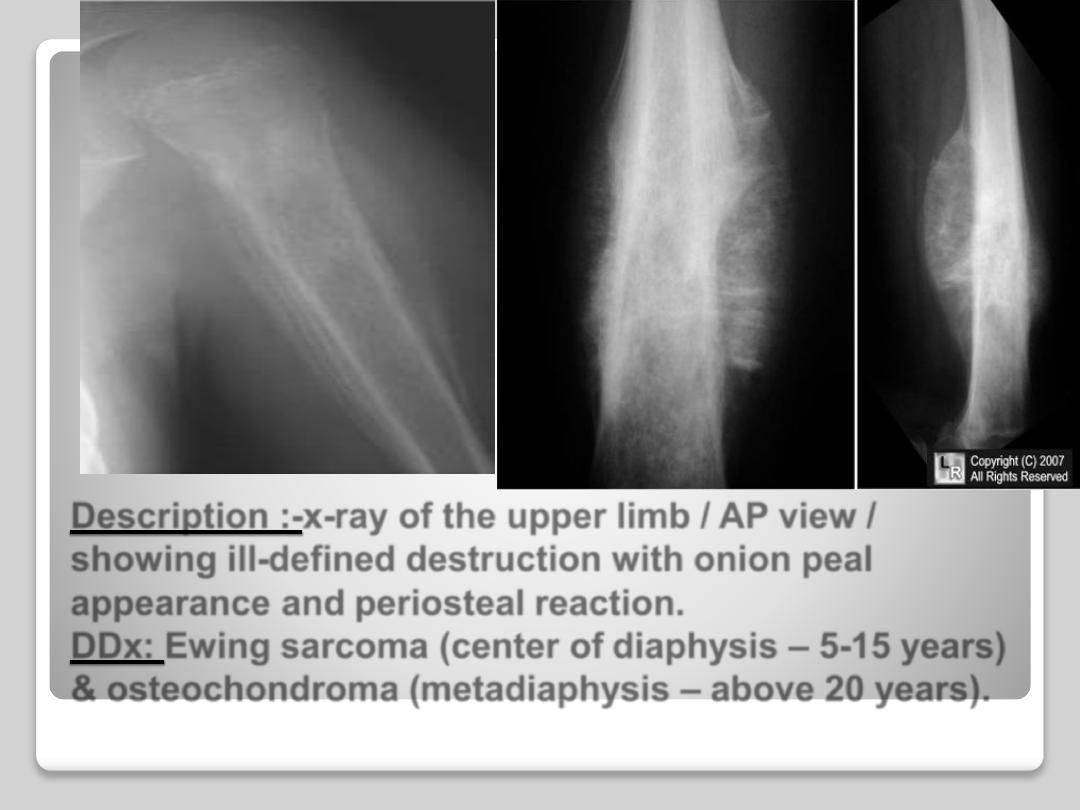

Description :-x-ray of the upper limb / AP view /

showing ill-defined destruction with onion peal

appearance and periosteal reaction.

DDx: Ewing sarcoma (center of diaphysis

– 5-15 years)

& osteochondroma (metadiaphysis

– above 20 years).